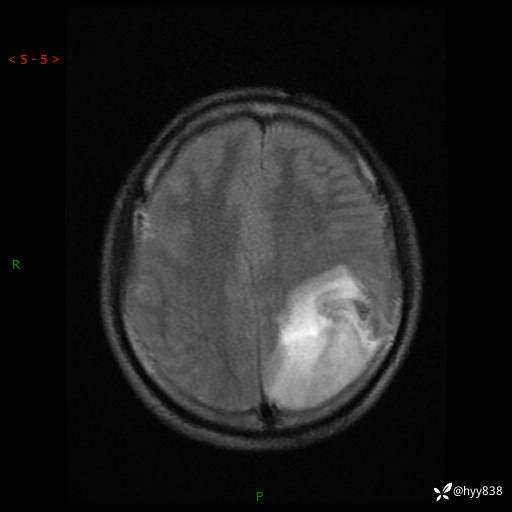

性别:男

年龄:21岁

简要病史:头痛伴呕吐半年,渐进性加重1月

颅脑MRI平扫+增强